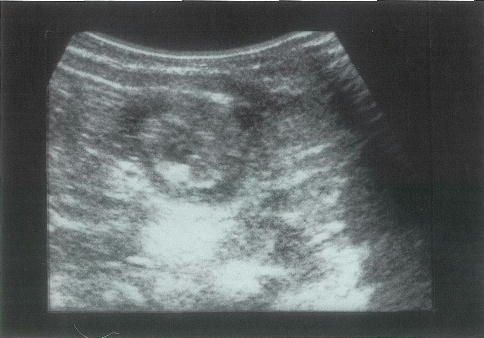

8か月の乳児。不機嫌と哺乳不良とを主訴に来院した。数日前から鼻汁があったが機嫌は良好であった。10時間前から急に不機嫌になりミルクを嘔吐するようになった。心音と呼吸音とに異常を認めない。右上腹部に腫瘤を触知する。腹部超音波写真を別に示す。

次に行うのはどれか。

○ a

正解 a

診断 腸重積症